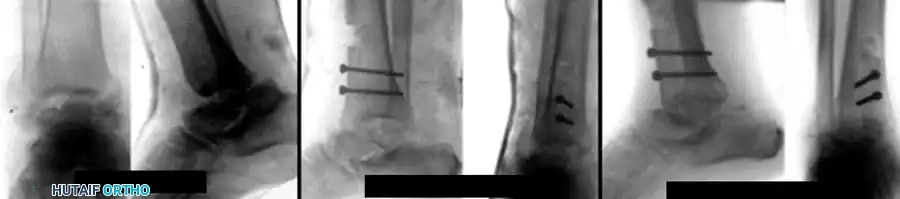

FIGURE 88-44: Results of Blair fusion. (A) Preoperative Type III fracture-dislocation of the talus with severe body comminution. (B) Immediate postoperative radiograph demonstrating the sliding anterior tibial graft slotted into the talar neck. (C) Solid fusion achieved at 3 months, preserving hindfoot height and subtalar kinematics.